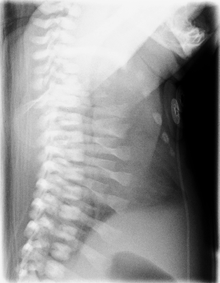

CXR of a newborn with asphyxiating thoracic dysplasia. Note the short ribs. | |

Jeune syndrome is a rare genetic disorder that affects the way a child’s cartilage and bones develop. It begins before the child is born. Jeune syndrome affects the child's rib cage, pelvis, arms and legs. Usually, problems with the rib cage cause the most serious health problems for children with Jeune syndrome. Their rib cages (thorax) are smaller and narrower than usual. This can keep the child's lungs from developing fully or expanding when the child inhales. The child may breathe rapidly and shallowly. They may have trouble breathing when they have an upper or lower respiratory infection, like pneumonia.